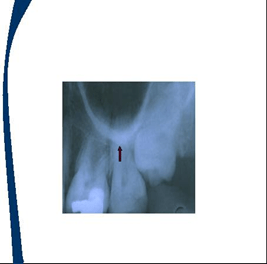

En las imagenes aparecen flechas que representan la localización de los landmarks o puntos de referencia

Espina nasal anterior